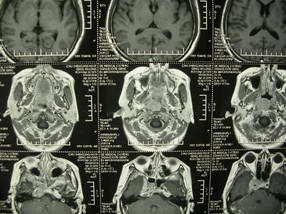

扫描示鼻咽腔不对称,中度狭窄,右侧咽隐窝消失,局部软组织肿块,鼻咽右侧壁增厚形成肿块,突入鼻咽腔,肿块平扫呈等密度,肿块向深部侵润,右侧翼内外肌受侵,右侧咽旁间隙变窄;向后生长,头长肌界线欠清,向后上生长侵犯同侧颈动脉鞘区。双侧海绵窦增宽,内见软组织影与鼻咽部肿块相连。考虑鼻咽癌。鼻咽癌主要是放射治疗,且效果较好;到当地有治疗设备较大医院治疗即可。

典型鼻咽癌侵犯右侧海绵窦(对放疗敏感)

还是先确诊,如果是鼻咽癌,一般行放射治疗;这例患者我首先考虑鼻咽癌